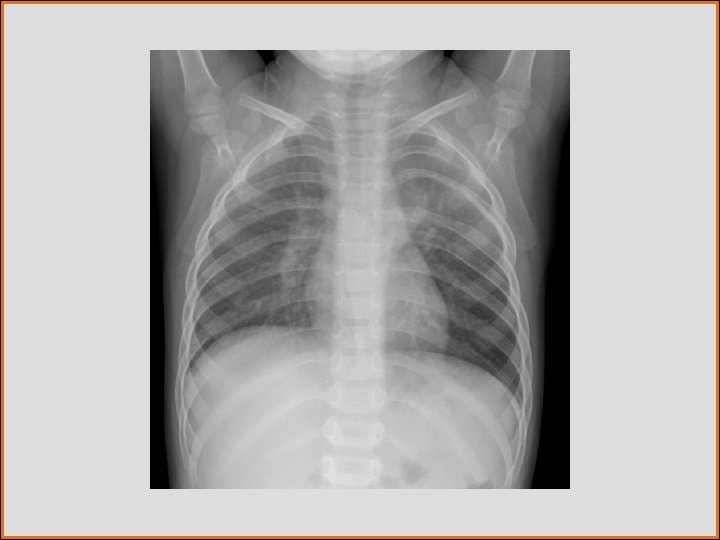

Case History • 3 -year-old male with cough

Test Your Diagnosis Which feature(s) is(are) present? a. Alveolar opacity b. Rib splaying c. Paraspinal mass d. Ectatic aortic arch

FINDINGS • Left paraspinal mass • Rib splaying